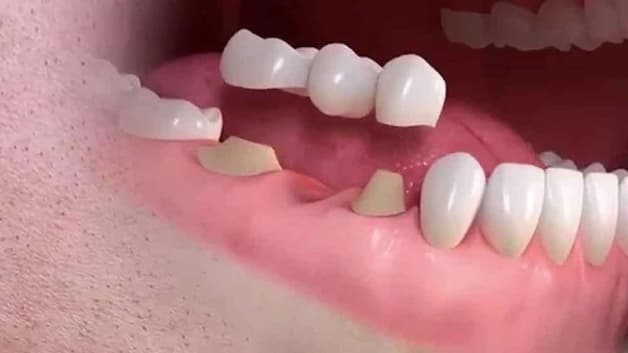

Khi sâu răng đã vào tủy, bệnh nhân cần nhổ răng rồi thực hiện phục hình răng để điều trị, tránh ảnh hưởng răng xung quanh

Với những trường hợp sâu răng đã vào tới tủy thì cấu trúc chân răng đã bị phá hủy nghiêm trọng. Lúc này, hàn trám không thể đem tới hiệu quả điều trị tốt. Nguyên nhân là do chức năng của răng bị sâu đã bị ảnh hưởng nhiều, không thể cải thiện. Trong trường hợp này, nhổ bỏ răng và phục hình răng mới là phương pháp thường được chỉ định. Như vậy, nguy cơ lây lan vi khuẩn sâu răng sang các răng bên cạnh sẽ được hạn chế. Những hiện tượng tiêu cực như viêm, nhiễm trùng ổ răng, lệch khớp cắn, … cũng sẽ được ngăn ngừa tối đa.